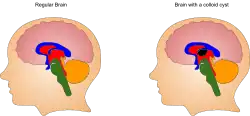

A colloid cyst is a non-malignant tumor in the brain. It consists of a gelatinous material contained within a membrane of epithelial tissue. It is almost always found just posterior to the foramen of Monro in the anterior aspect of the third ventricle, originating from the roof of the ventricle. Because of its location, it can cause obstructive hydrocephalus and increased intracranial pressure. Colloid cysts represent 0.5–1.0% of intracranial tumors.[1]

Patients with third-ventricular colloid cysts become symptomatic when the tumor enlarges rapidly, causing cerebrospinal fluid (CSF) obstruction, ventriculomegaly, and increased intracranial pressure. Some cysts enlarge more gradually, however, allowing the patient to accommodate the enlarging mass without disruption of CSF flow, and the patient remains asymptomatic. In these cases, if the cyst stops growing, the patient can maintain a steady state between CSF production and absorption and may not require neurosurgical intervention.[4]